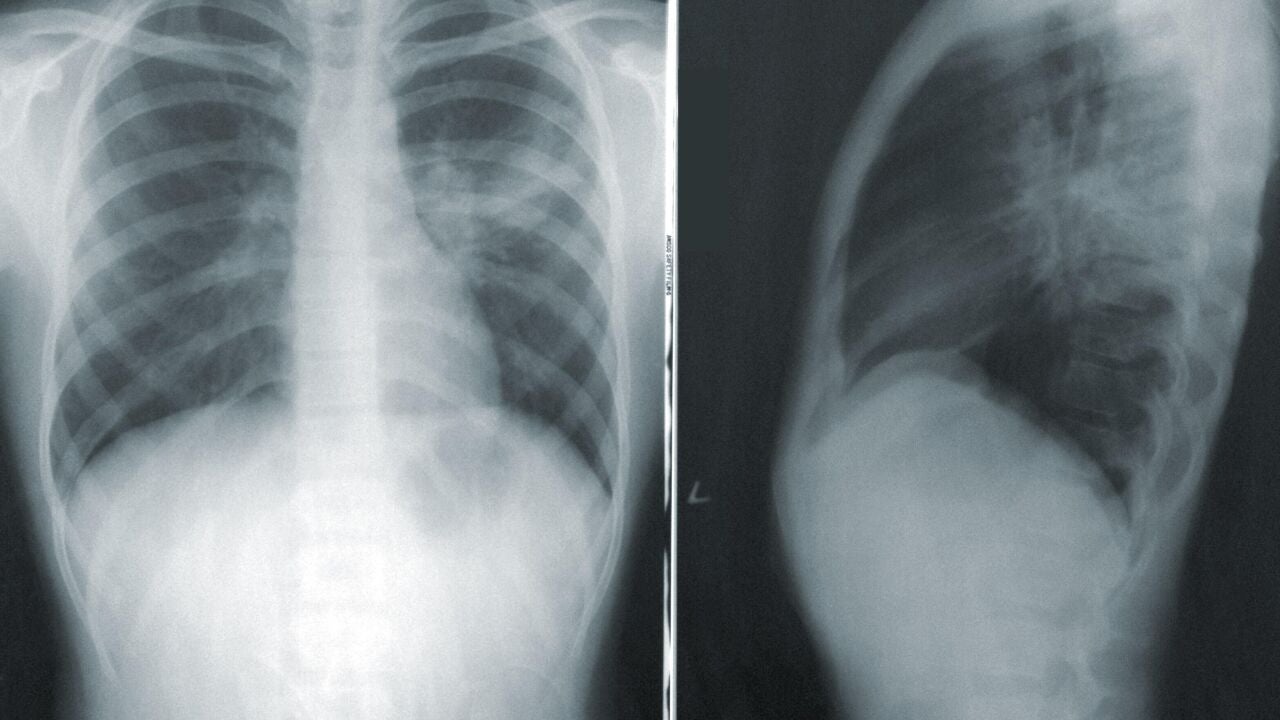

Radiografía de un torsoCDC para Unsplash

En la reunión anual de la Sociedad Radiológica de América del Norte, RSNA, un grupo de científicos ha presentado un modelo de aprendizaje profundo que utiliza una sola radiografía de tórax para predecir el riesgo de muerte y otras enfermedades en el plazo de diez años. Entre las posibles patologías que puede detectar están un ataque cardíaco o un derrame cerebral, derivado de la enfermedad cardiovascular aterosclerótica.

Este modelo de aprendizaje profundo está creado a partir de inteligencia artificial entrenada para analizar imágenes tomadas por rayos X. "Nuestro modelo de aprendizaje profundo ofrece una solución potencial para la detección oportunista basada en la población del riesgo de enfermedad cardiovascular utilizando imágenes de rayos X de tórax existentes", señaló el autor principal del estudio, Jakob Weiss, del Centro de Investigación de Imágenes Cardiovasculares de Massachusetts, Estados Unidos.